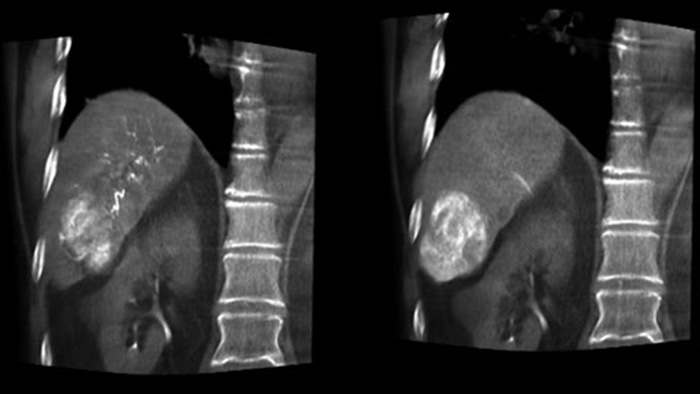

Ao abrir o arco à esquerda do paciente, a CBCT Aberta permite o posicionamento do paciente na mesa fora do centro e, portanto, uma melhor centralização do FOV3-4, aumentando significativamente a cobertura da imagem para ajudar a visualizar tumores na periferia do fígado.4